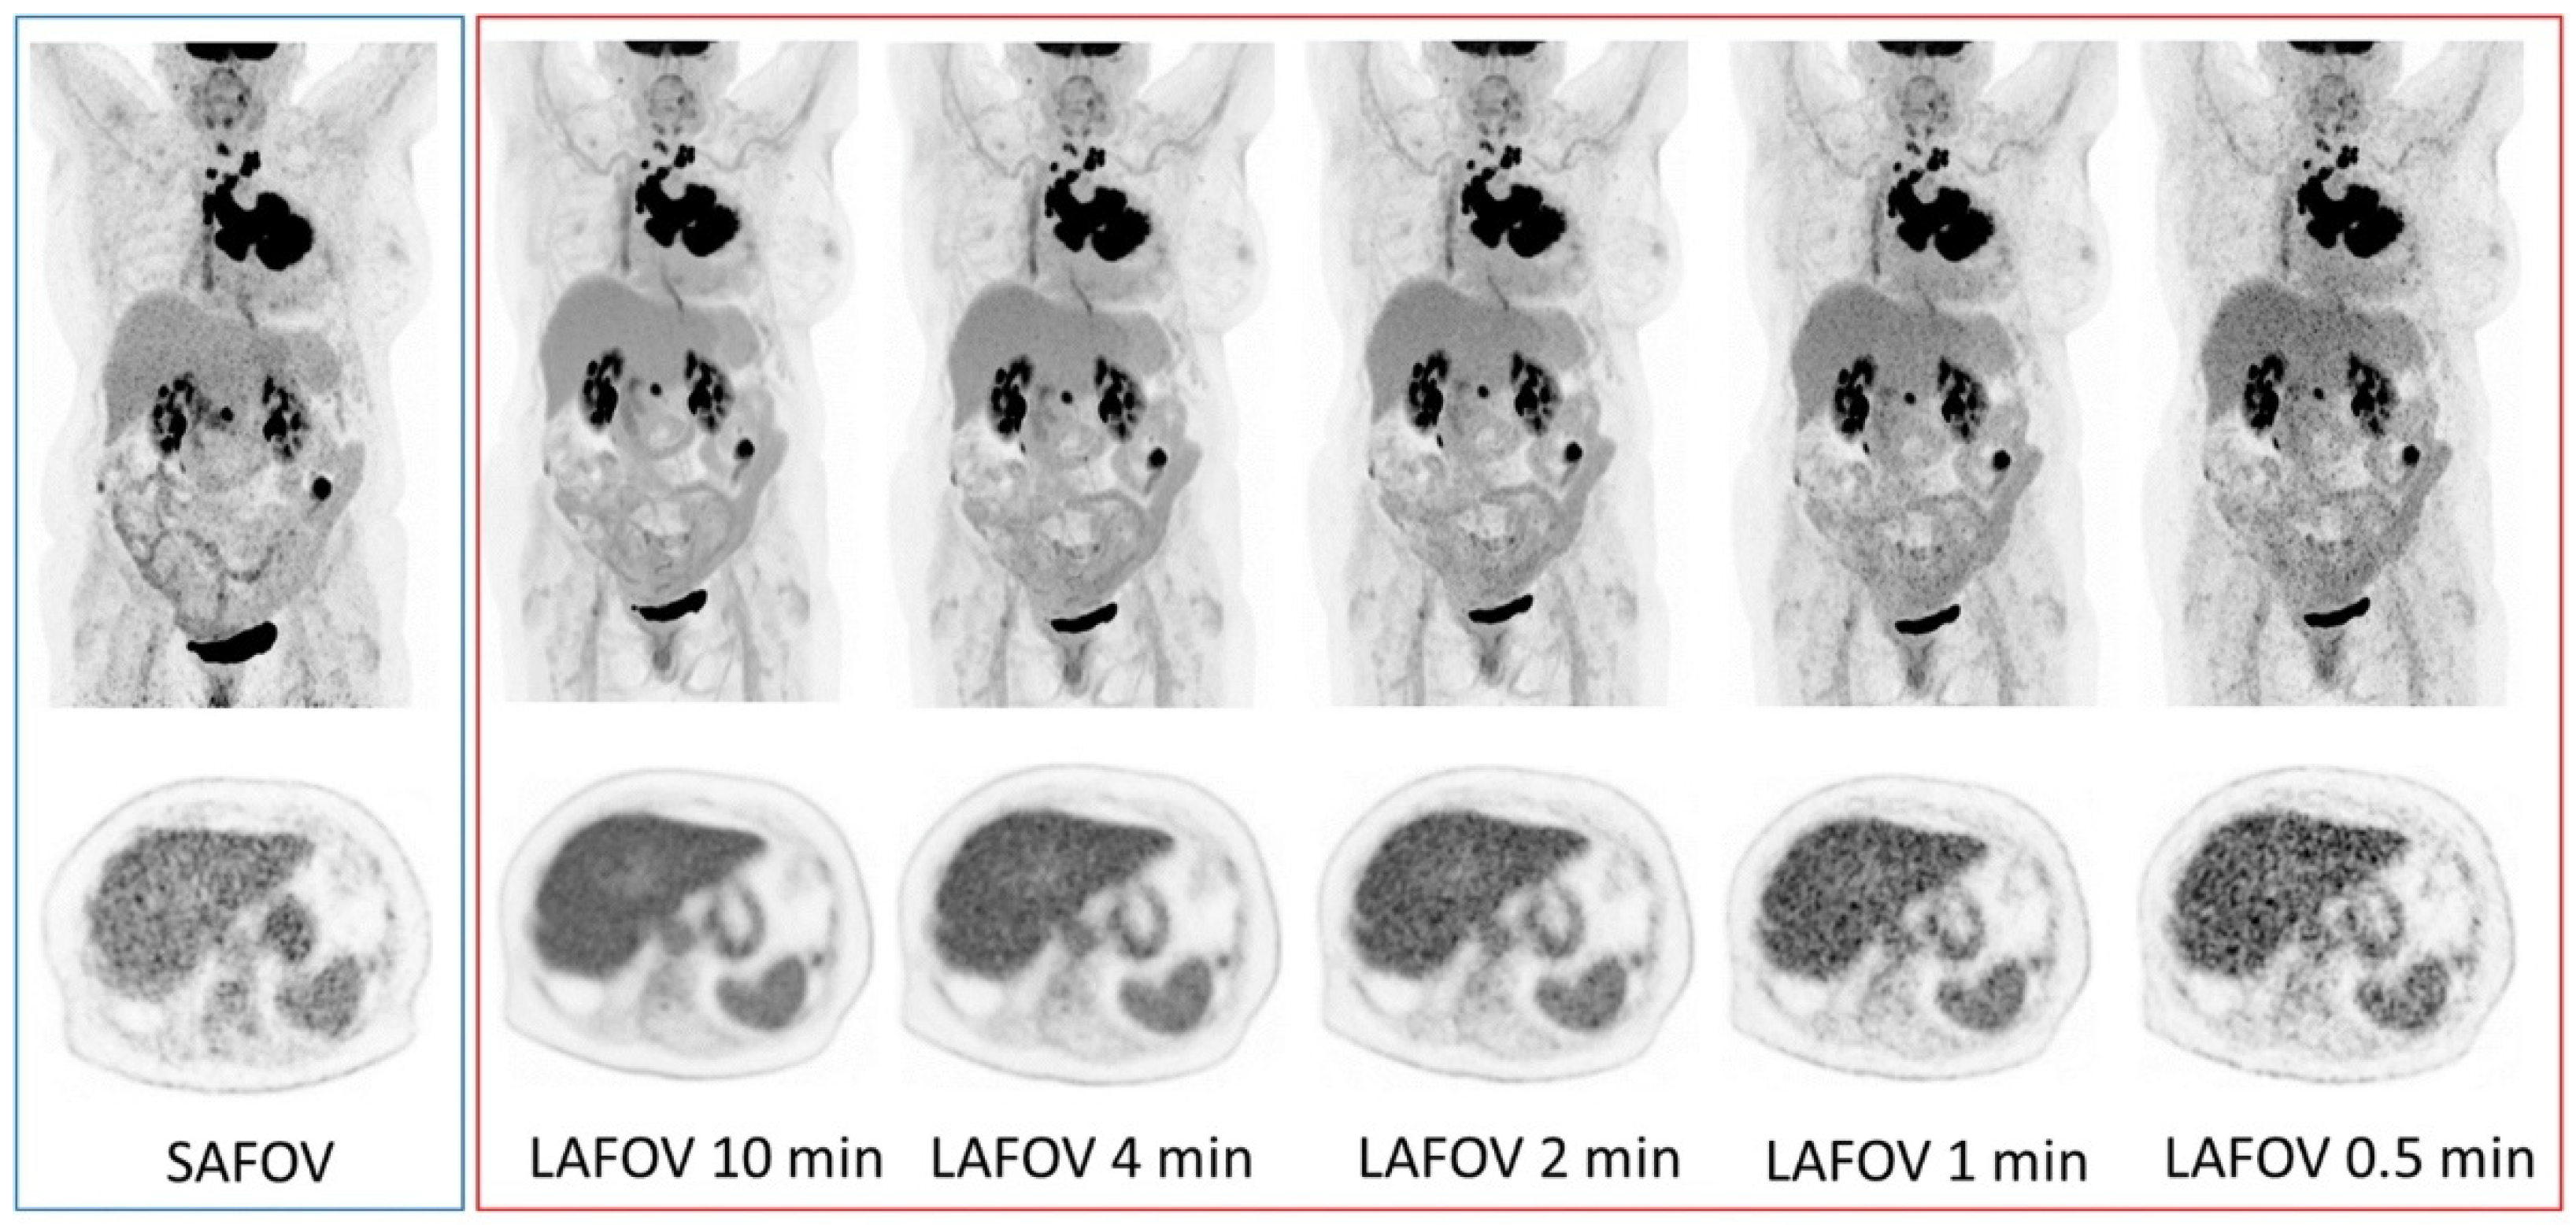

- Alberts, I.; Hünermund, J.N.; Prenosil, G.; Mingels, C.; Bohn, K.P.; Viscione, M.; Sari, H.; Vollnberg, B.; Shi, K.; Afshar-Oromieh, A.; et al. Clinical performance of long axial field of view PET/CT: A head-to-head intra-individual comparison of the Biograph Vision Quadra with the Biograph Vision PET/CT. Eur. J. Nucl. Med. Mol. Imaging 2021, 48, 2395–2404. [Google Scholar] [CrossRef]